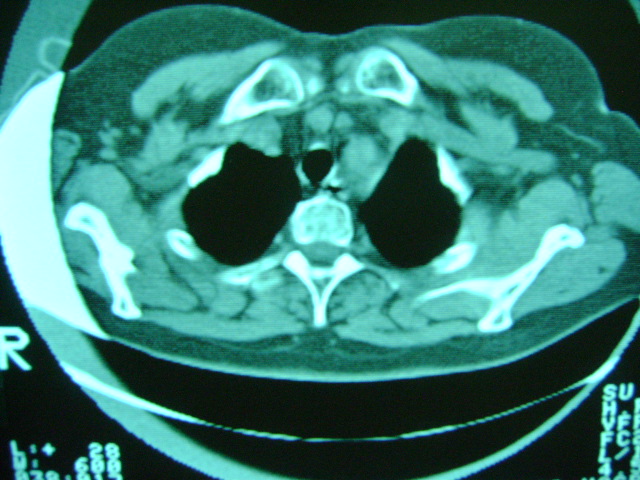

朋友的母亲,56y,咳嗽三个月,感觉左肺门不对,请大家给点意见

老年人,肺动脉略迂曲